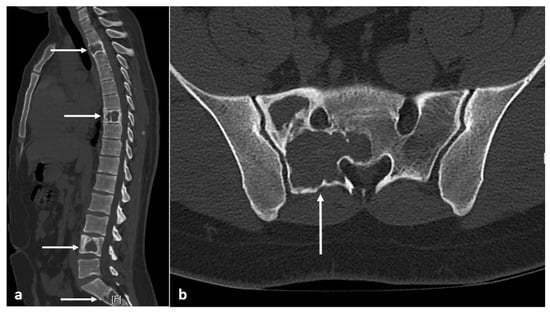

| Fibrous dysplasia | Ground glass matrix. Cystic areas can appear lytic. | Low on T1 and intermediate to high on T2. Cystic areas are hyperintense on T2 and STIR. |